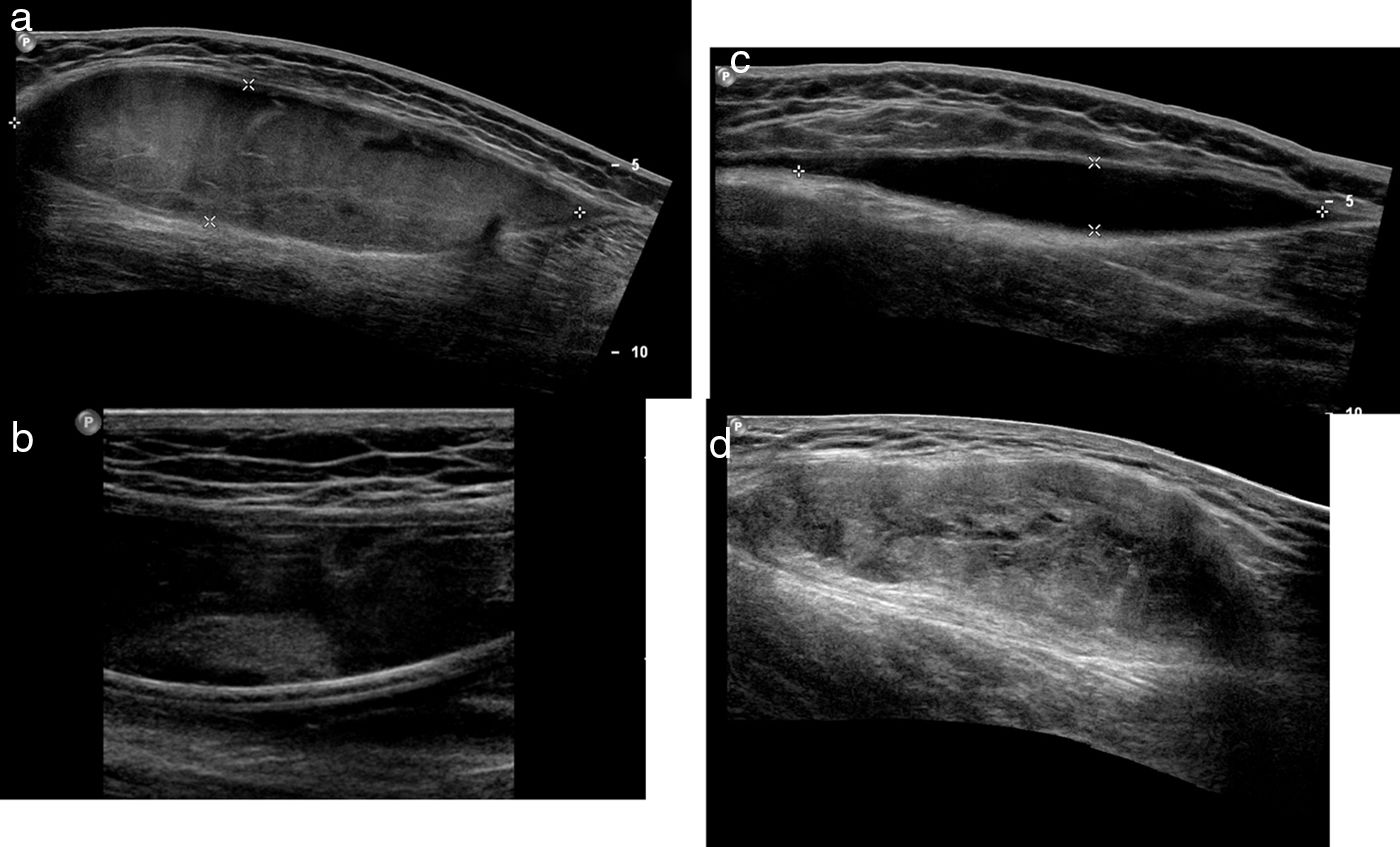

We aim to review the characteristics of Morel-Lavallée lesions and to evaluate their treatment.

Material and methodsWe retrospectively reviewed 17 patients (11 men and 6 women; mean age, 56.1 years, range 25–81 years) diagnosed with Morel-Lavallée lesions in two different departments. All patients underwent ultrasonography, 5 underwent computed tomography, and 9 underwent magnetic resonance imaging. Percutaneous treatment with fine-needle aspiration and/or drainage with a 6–8F catheter was performed in 13 patients. Two patients required percutaneous sclerosis with doxycycline.

ResultsAll patients responded adequately to percutaneous treatment, although it was necessary to repeat the procedure in 4 patients.

ConclusionsRadiologists need to be familiar with this lesion that can be treated percutaneously in the ultrasonography suite when it is not associated with other entities.